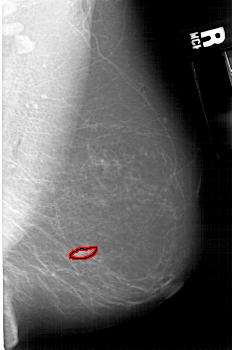

LEFT_MLO LINES 5296 PIXELS_PER_LINE 3721 BITS_PER_PIXEL 12 RESOLUTION 43.5 NON_OVERLAY

FILE: A_1593_1.RIGHT_MLO.OVERLAY

TOTAL_ABNORMALITIES 1

ABNORMALITY 1

LESION_TYPE MASS SHAPE FOCAL_ASYMMETRIC_DENSITY MARGINS ILL_DEFINED

ASSESSMENT 4

SUBTLETY 2

PATHOLOGY MALIGNANT

TOTAL_OUTLINES 1

BOUNDARY